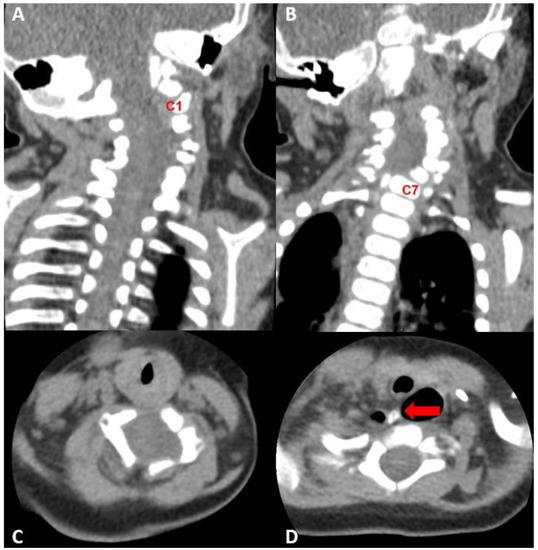

2.3. Diagnostic Assessment